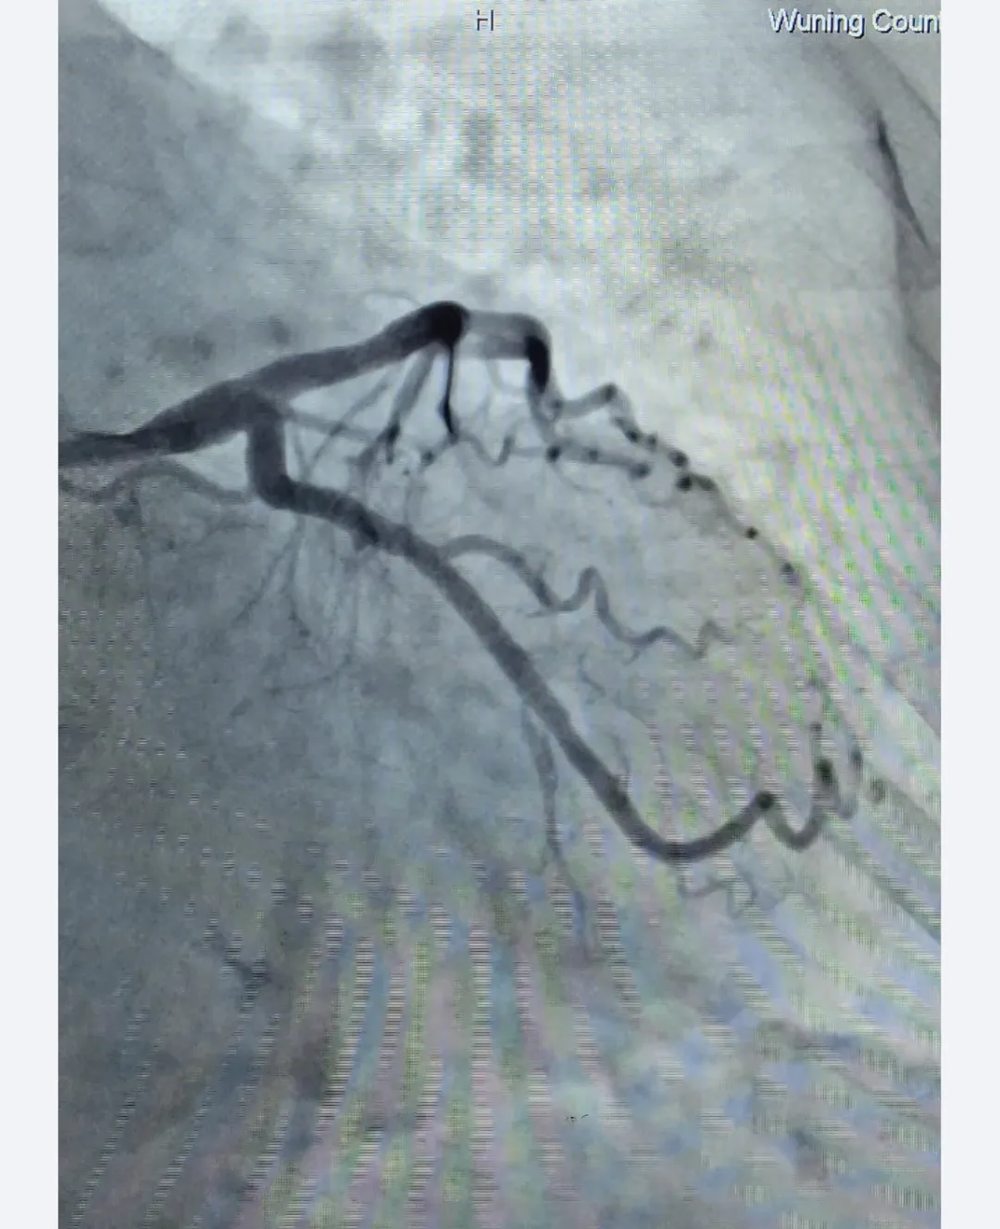

手术前

支架植入后